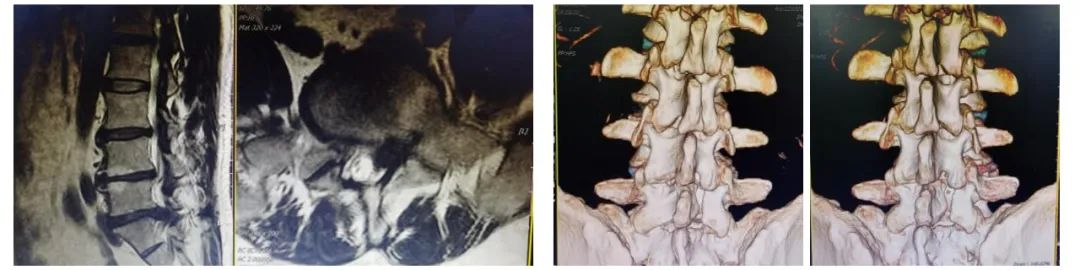

术前影像学检查:腰5/骶1椎间盘突出症术后改变,腰5/骶1椎间盘突出术后再复发

脊柱外科微创团队对患者详细查体后,进行病例讨论,详细阅读患者既往及本次入院后影像学资料,针对患者要求微创手术治疗的诉求,最后讨论一致同意为该患者实施单侧双通道脊柱内镜下椎管扩大减压、腰5/骶1椎间盘摘除、椎间融合器植骨融合+经皮螺钉内固定术;UBE(单侧双通道脊柱内镜)镜下椎管扩大减压、椎间盘摘除及椎间融合植骨融合在我科已成熟开展,并常规应用于腰椎管狭窄症微创治疗;脊柱翻修病例的复杂性在脊柱外科领域实属难题,微创内镜下更极具挑战!